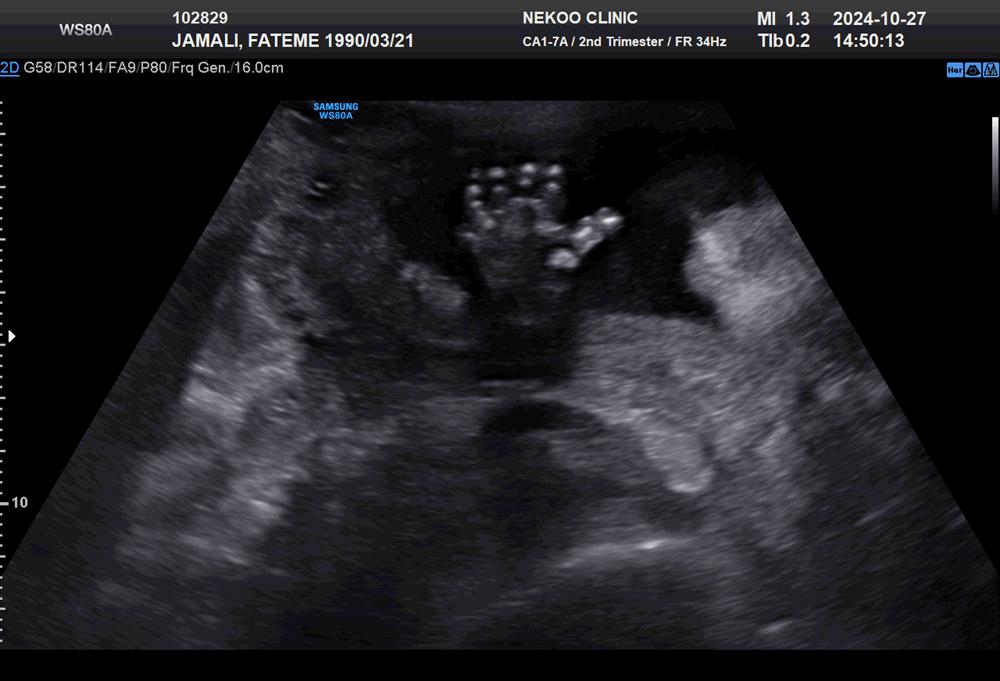

سلام دکتر من هفته ۱۸بارداری آنومالی دادم بخاطر کیست دکترم مجدد نوشت و انجام دادم هفته پیش یعنی ۲۴هغته دیروز پیش دکترم بودم سونو رو دیدن وگفتن خداروشکر برطرف شده و جنین مشکلی ندارد خداروشکر اما توی برگه سونو عکس اسکن نزدن بصورت لینک برام فرستادن حالا من سونورو میبینم یعنی عکس بابت انگشتان دستش نگرانم همش استرس ونگرانی دارم که مبادا ۶انگشتی باشد. درحالی که اگه چیزی بود توی برگه مینوشتن اگه امکانش هست بفرستم بررسی کنید ممنونم خیلی استرس دارم

اولا که نه اینطور نیست ۵تا رشد کردن و اون شایدبخاطر عکس سونو باشه

خواهر من عیب روبچه نزار عکس تار افتاده.

جانم سایه و کنتراست عکس هست اگر موردی بود در گزارش ذکر میشد نگران نباشید ❤️😘